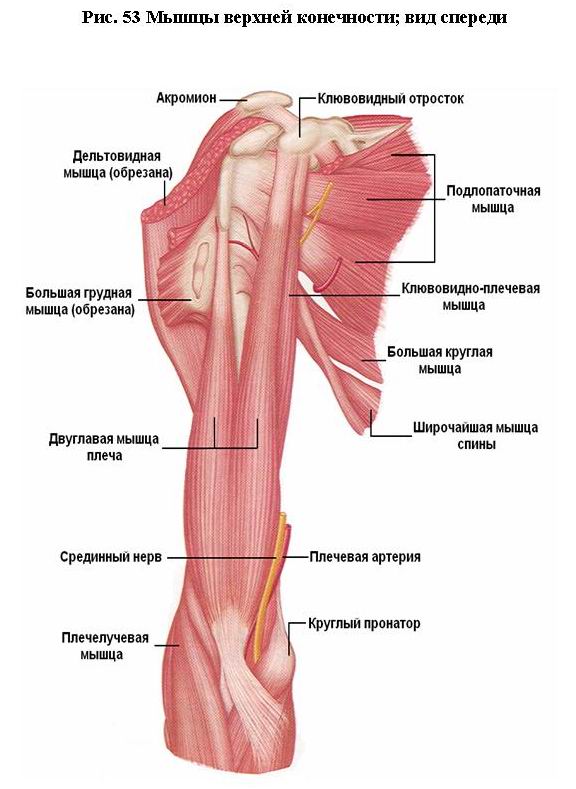

Фотографии поддельтовидной мышцы плечевого сустава